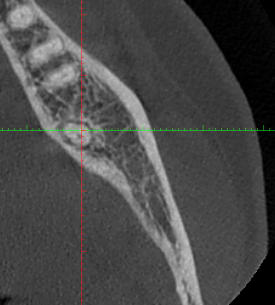

J'aimerais votre avis pour ce cas. Je suis sûre à 99% qu'il faille dévitaliser la 37 suite à pour moi un abcès apical aigu mais je ne trouve pas de réelle cause et j'aimerais savoir si vous aviez une idée.

Atcts ; Chimio (plus de souvenir de la molécule) en 2018 + radiothérapie pour cancer endomètre.

09/06 : 37 a eu petite gene dernierement a la mastication très léger par moment. Tartre ++ en occlusal de 27 je pense à une sur sollicitation. Elargissement desmodontal sur la radio mais froid positif donc surement traumatique par surocclusion? Si perdure peut etre fracture? A ré évaluer.

07/07 37 : douleur type abcès apical aigu il y a 2 semaines calmées par les ATB. // Scan pour recherche origine fracture, RAS. Test au froid clairement négatif cette fois (on en a reparlé il lui semble vraiment qu'elle sentait le froid la fois d'avant... ) Mobilité 2 de la dent. Plus de tartre antagoniste. La patiente rapporte beaucoup bruxer, on fait donc une gouttière.

Elle est necrosee ca se voit sur la pano à l apex

Il n y a pas 500 possibilités il n y a pas de carie pas de fracture car pas d image en doigt de gant et de signe clinique de fracture ... il reste a mon humble avis que des surcharges de forces peut etre légères et répétées antérieures car pas de surocc a priori

Probable trauma, violent ou modéré mais chronique, ayant entrainé fêlure puis nécrose.

Je confirme l'avis de Thierry, les fêlures ne se voient souvent pas, pas plus à la radio 3D d'ailleurs.

Si test au froid négatif, l'image à la radio ne fait aucun doute: c'est nécrosé, faut dévitaliser.

J'ai constaté qu'avec cette morphologie de racine pour les 7 mandibulaires on avait un risque accru de fêlures fractures.